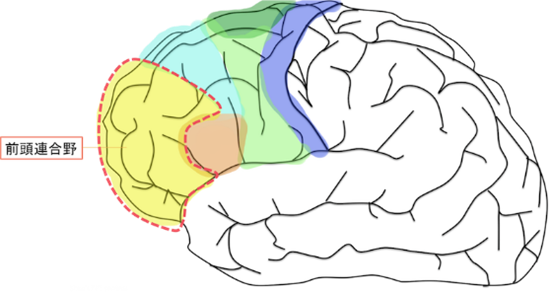

「前頭葉」は、脳の前方部に位置しています。

ここは重要な神経が密集した部位です。

「前頭葉」は、前方部にある「前頭連合野」と「運動前野」「補足運動野」などがありますが、最前方に位置する「前頭連合野」(前頭前野とも呼ばれます)が、老化に大きく関わるように思われます。

前頭連合野

前頭連合野は前頭前野とも呼ばれます。

前頭葉は、大脳の中心溝よりも前の部分で、「前頭連合野(前頭前野)」「高次運動野」「一次運動野」の3つに分けられます。

人間性(人間らしさ)を保てるのは、前頭葉が機能しているからで、ここが障害されると、異常行動や異常発言が目立ち、人間らしさを失っていきます。

悪いことを悪いと判断できなくなり、物事を計画することや、理解することができなくなります。

それ故、「別人格になってしまった」と周囲には思われてしまいます。

穏やかだった人が、別人格のように攻撃的になることもあり得ます。

ここでは、混乱しますので、すべて「前頭葉」として表示します。

この「前頭葉」には、ヒトが人であるための人間らしさ(人間性)を司る部位です。